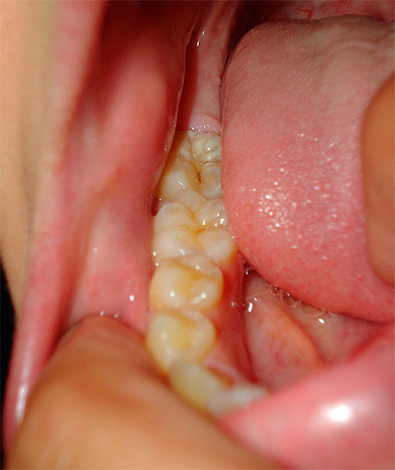

A foto abaixo mostra um exemplo de um cisto enorme, que não foi removido em tempo hábil e, tendo aumentado em volume, cresceu até as raízes de um dente adjacente: